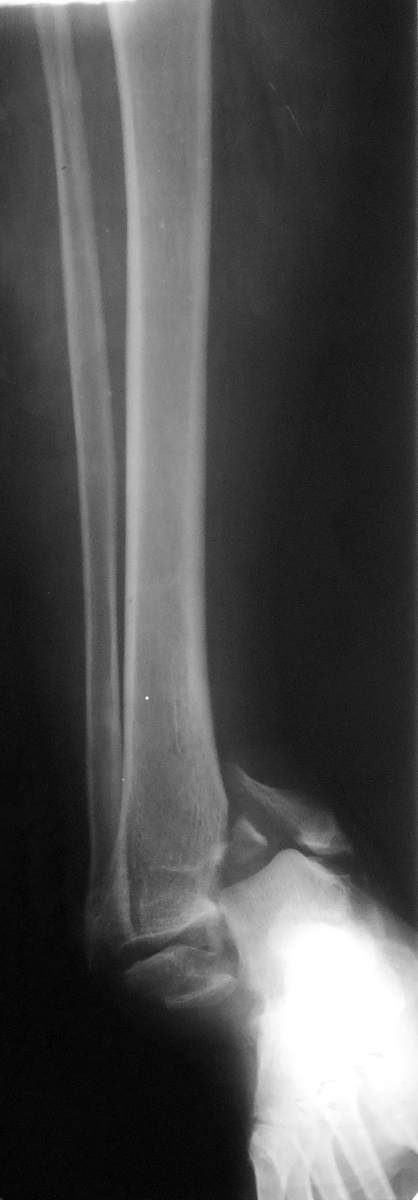

В приложении рентгенограмма первичная. После чего стала ясна

сомнительность перелома пилона))) Перелом лодыжек с импрессией суставной

поверхности большеберцовой кости в области внутренней лодыжки. На

выполненном вчера КТ голеностопного сустава: в просвете сустава

определяется клиновидной формы фрагмент костной плотности размером до

13,5х3,5 мм, находящийся в задне-латеральных отделах сустава.